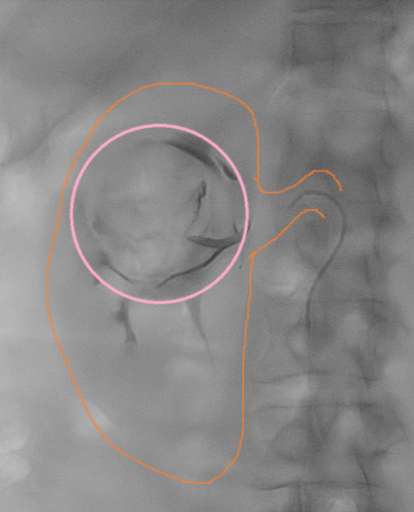

תמונות מההליך

שלבי הפעולה:

- הדגמת סלקטיבית של ה-AML בכליה הימנית. עושר של עורקים מפותלים ומורחבים (tortuous feeding vessels), היעדר מבנה קפילרי תקין, הסתעפויות לא סדירות מבנה זה מסביר את הנטייה לדימום ספונטני.

- הדגמת של הכליה וה-AML בכליה הימנית. הכליה נצבעת בחומר הניגוד בעצה רבה יותר מאשר ה-AML.